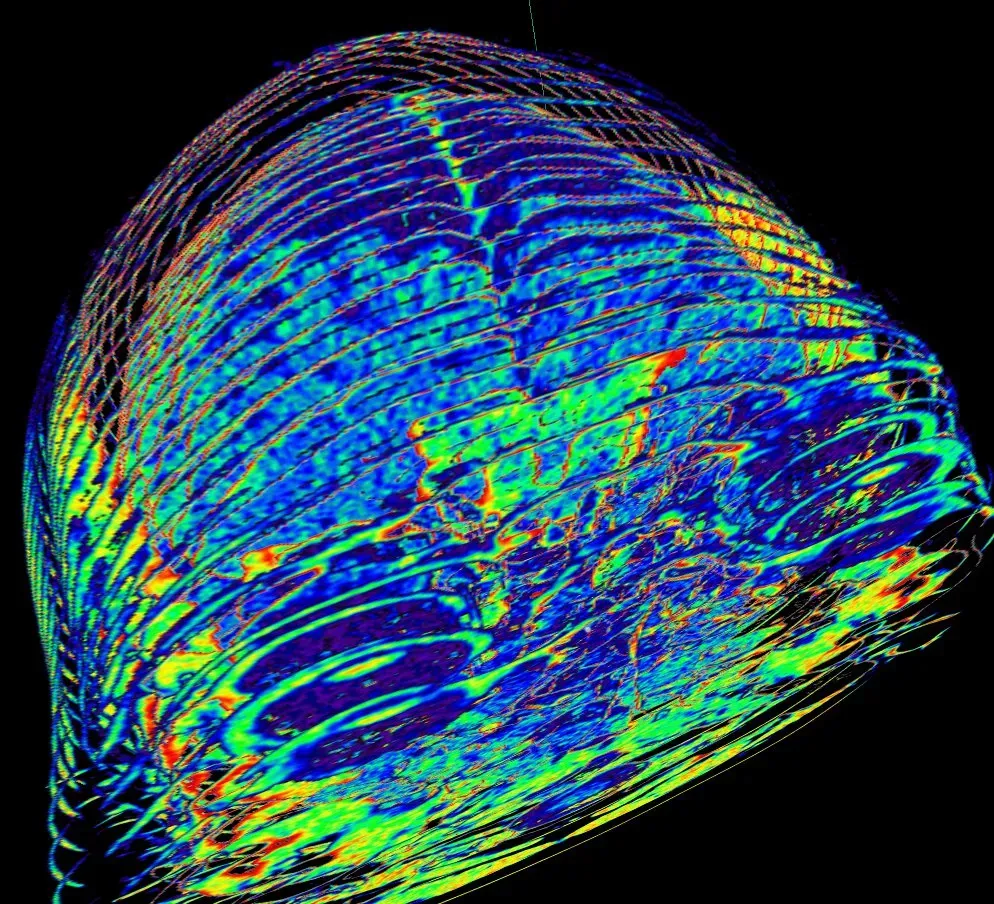

Powerful tools like EEG, MRI, and optogenetics changed the game by giving scientists direct access to brain activity in real time. Researchers could switch specific circuits on or off in animals and watch behaviors flicker in and out, or scan the brains of patients under anesthesia and see consciousness seemingly drain away. It was tempting to assume that if we could just refine the technology – sharper images, faster recording, better models – awareness would eventually be revealed as a straightforward brain function. Instead, the better our tools became, the clearer the gap looked between mapping neural activity and explaining subjective experience. It is as if we built better and better telescopes, only to discover the universe is stranger than we hoped.

Neuroscience is not short on theories of consciousness; it is short on decisive evidence that favors one view over the others. Some frameworks argue that awareness emerges when information in the brain becomes globally available, broadcast across widely connected networks that allow perception, memory, and decision-making to interact. Others suggest that consciousness arises from highly integrated information, where the whole system does more than the sum of its parts, in a way that cannot be broken down into independent components. A third family of ideas focuses on specific patterns of feedback loops and recurrent processing, claiming that awareness shows up when signals do not just flow forward but loop back in structured ways.

Looking ahead, the search for awareness is likely to become even more interdisciplinary and technologically bold. New brain–computer interfaces promise to record from and stimulate massive numbers of neurons simultaneously, giving scientists a chance to manipulate patterns of activity with unprecedented precision. Advanced imaging could link these micro-level manipulations to large-scale brain dynamics, while computational models attempt to simulate what happens when certain circuits are pushed into or out of conscious states. There is a real possibility that we will soon be able to toggle specific kinds of experience in animals and, one day, in consenting humans.